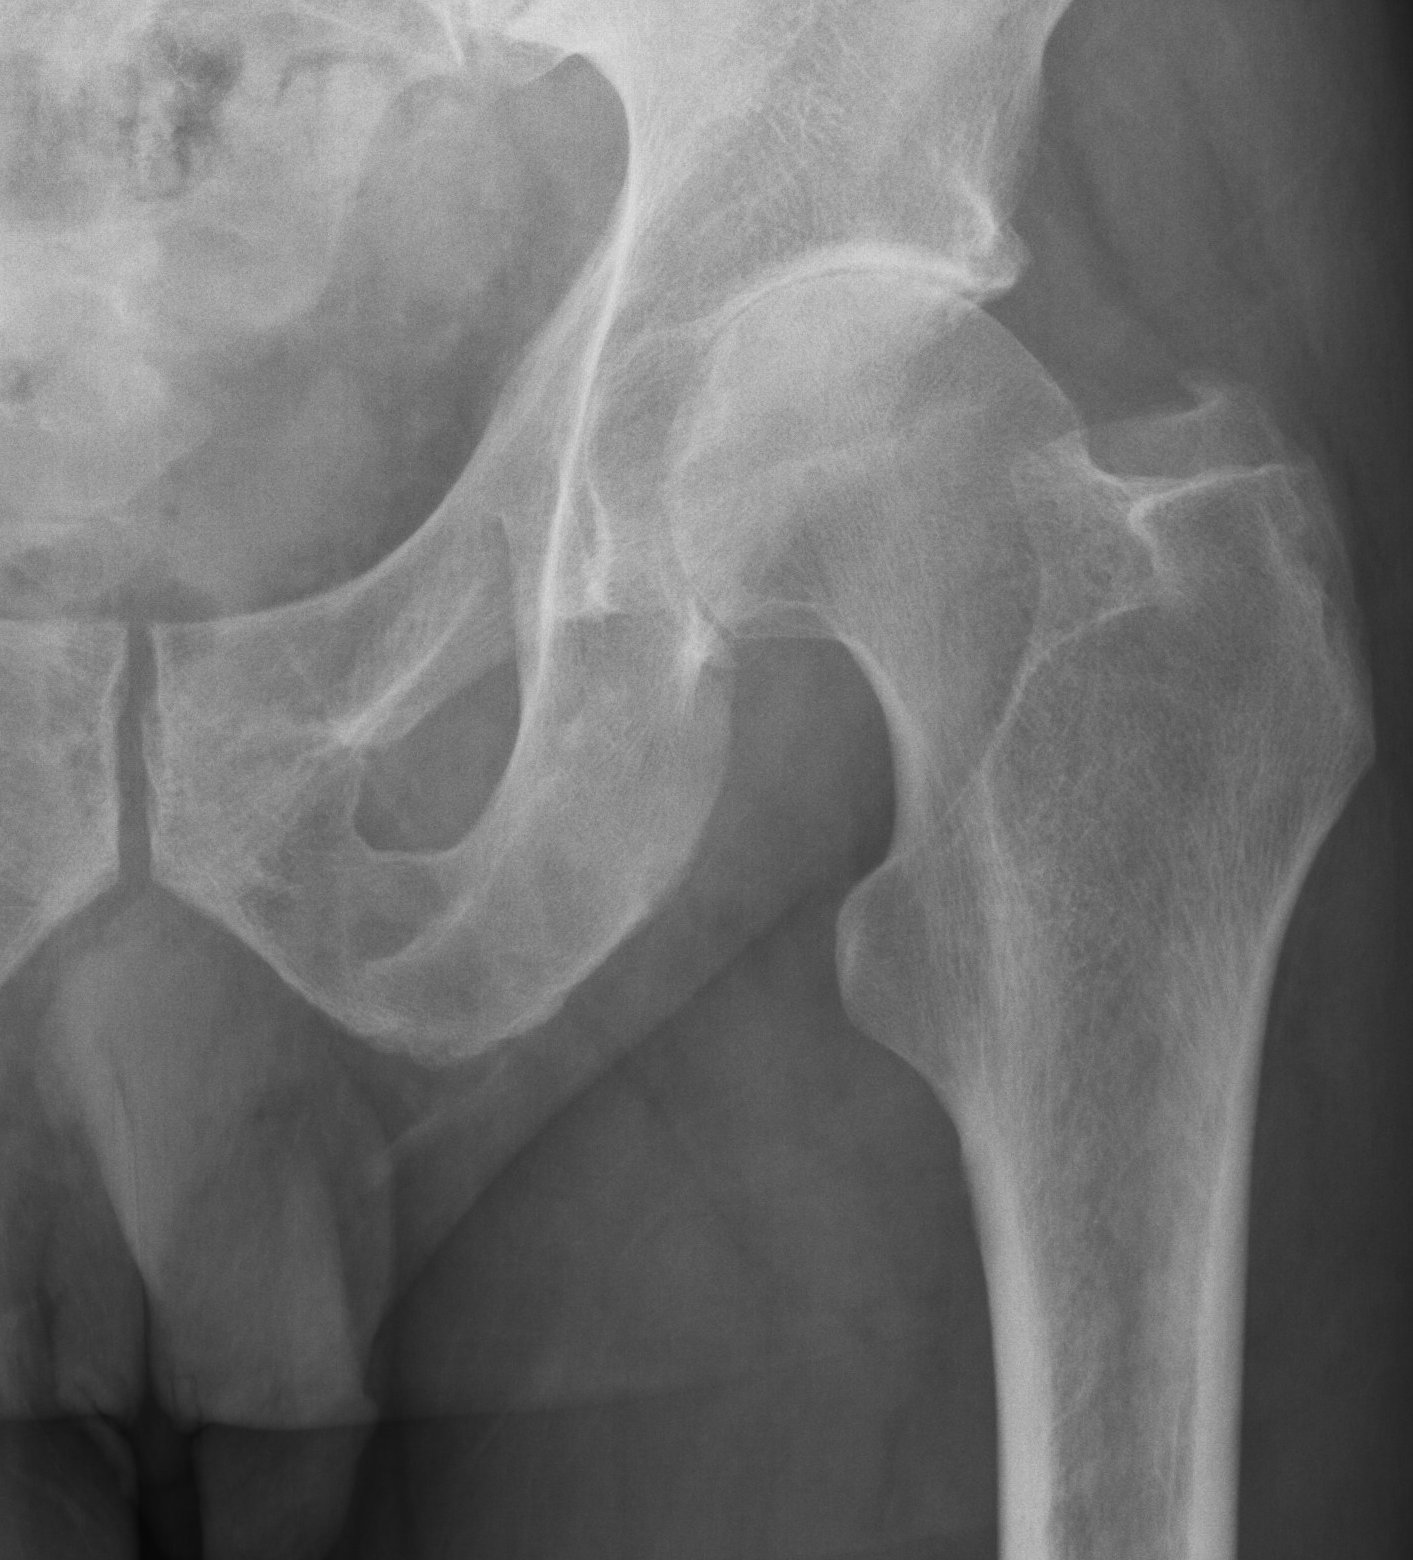

Patients usually present with a very rapid onset of severe pain and signs of toxicity. In patients who are very immuno-compromised there may not be the usual signs of systemic reaction to infection. In the early stages x-rays may mimic arthritis or AVN.

MRI is very sensitive but may still struggle to differentiate between advanced sepsis and AVN.

Aspiration of the hip joint, with x-ray control is the diagnostic test of choice. Staphylococcus aureus continues to be the most common organism isolated from adult hips affected by sepsis. Rarely, spontaneous nongonococcal and Candida sepsis of the hip joint in otherwise healthy adults have been reported.  Gonococcal septic hip arthritis is less common, and it is usually associated with specific host risk factors.